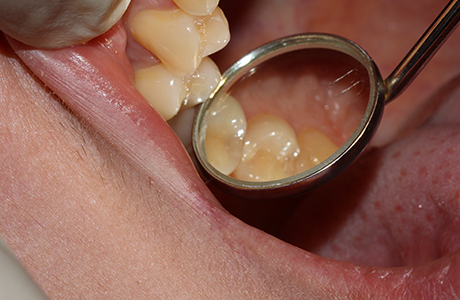

В клинику обратилась пациентка с жалобой на чувствительность зубов к холодному. Боль острая и быстро проходящая. Из других симптомов: неприятный запах изо рта после использования флосса в районе 14 и 15 зубов. В ходе осмотра врач стоматолог-терапевт Похилько Надежда Геннадьевна поставила диагноз — хронический глубокий кариес 14 и 15 зубов.

Глубокий кариес поражает твёрдые ткани зуба, в частности, дентин. Такое заболевание характеризуется кратковременной острой болью в качестве реакции на температурные изменения пищи. При отсутствии лечения глубокий кариес переходит в пульпу, в результате чего вызывает развитие пульпита.

В ходе лечения врач провёл следующие манипуляции:

- лечение кариозных полостей 14 и 15 зубов с использованием светоотверждаемого композита Эстелайт;

- медикаментозная обработка;

- установка пломбы.